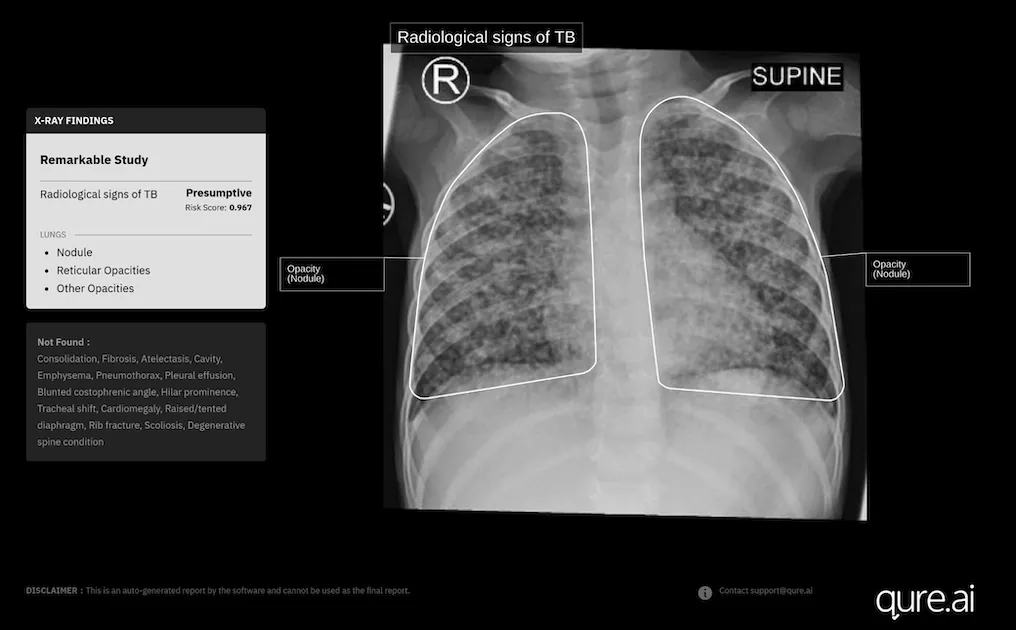

Its chest X-ray analysis AI tool is the first to receive Europe's clearance for use in children aged 0-3.

Indian medical imaging AI company Qure.ai has secured new approval in Europe for the expanded use of its chest X-ray analysis AI tool to diagnose paediatric tuberculosis in toddlers.

It has recently received a new CE Mark under the European Union's Medical Device Regulation for the use of its AI-powered chest X-ray software, qXR, in children aged 0-3 years.